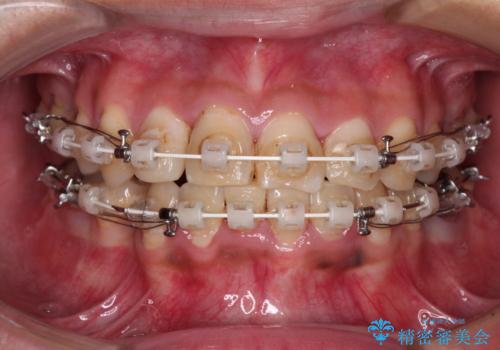

- 矯正装置

- 審美装置

- 治療期間

- 2年4ヶ月

第二小臼歯抜歯の矯正治療は、治療期間が長引くことが多いですが、動きが非常に良く、予定の治療期間で終えることができました。